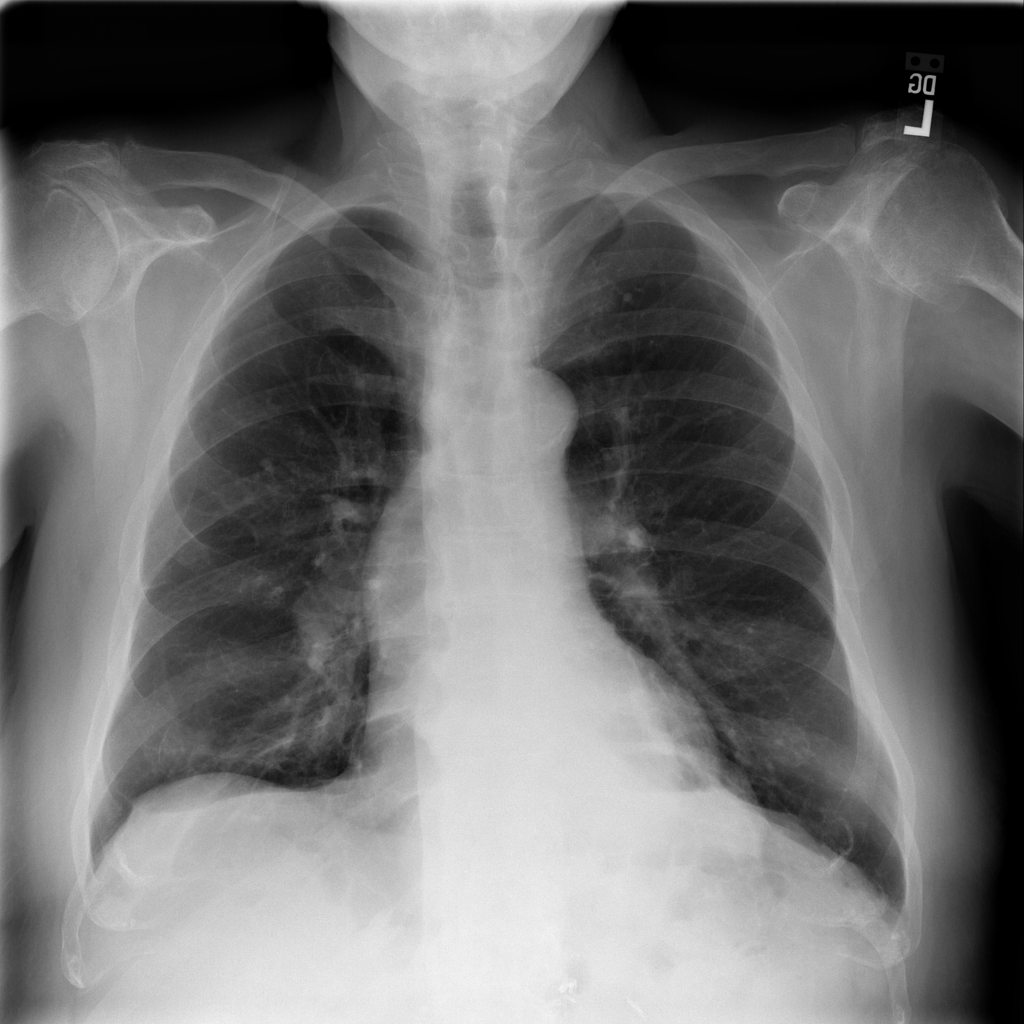

Showing up to 90 reference images for Hernia.

PAT-4F7E · IMG-000Hernia

PAT-4F7E · IMG-000

PA